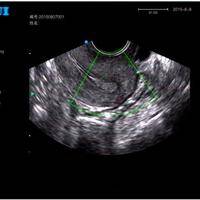

子宫内膜息肉的术前禁忌和术后护理

子宫内膜息肉是由于宫内膜增生过盛造成的,任何年龄均可发生,是常见的局限性内膜肿物,突出于子宫腔内、光滑、肉样硬度,蒂长短不一,长者可突出于宫颈口外。该病可引起不规则阴道流血、不孕,目前病因未明,认为与内分泌紊乱有关,以超声诊断为主,子宫声学造影敏感性更高,宫腔镜是诊断子宫内膜息肉的金标准,宫腔镜下息肉摘除术是子宫内膜息肉首选的治疗方法,但息肉易复发。子宫内膜息肉术前禁忌1、一般来说,患者在手术前不能吃东西。2、检查前48小时,不要使用卫生棉棒,避孕药或者相关产品。3、在检查前两天,不要享受泡泡浴等要在浴盆进行的洗澡方式,应该使用站立的淋浴方式。4、检查前48小时内,不要有性行为。5、在手术前...

子宫内膜息肉的原因子宫内膜息肉表现为局限性内膜肿物突出于子宫腔内,肿物呈灰红色、有光泽、质软、单个或多个。蒂长短不一,长者可突出于宫颈口外,镜下大多数内膜息肉是未成熟上皮,对孕激素不起反应,呈增生期改变,而其周围的子宫内膜已有分泌期改变。1、炎症因素长期患有妇科炎症的女性易导致子宫息肉,长期炎症刺激就会使息肉越来越大。2、内分泌紊乱子宫内膜息肉与雌激素水平过高有关,雌激素促进阴道、子宫、输卵管和卵巢本身的发育,同时子宫内膜增生而产生月经。子宫内膜仅受雌激素刺激,缺乏孕激素作用,导致子宫内膜无限制生长,则易产生息肉。3、病原体感染通常由分娩、流产、产褥期感染、手术操作或机械刺激、性交损伤子宫颈...

子宫内膜息肉是怎么回事

子宫内膜的厚度和子宫内膜的周期性变化是有关系的。子宫内膜的周期性变化包括子宫内膜的组织学变化和子宫内膜的生物化学变化。子宫内膜厚度多少正常和子宫内膜的组织学变化是有影响的。子宫内膜正常厚度根据周期不同,可以1-10mm。子宫内膜功能层是胚胎植入的部位,受卵巢激素变化的调节,具有周期性增殖、分泌和脱落性变化,具体组织学变化,将月经周期分为增殖期、分泌期和月经期三个阶段(以一个正常月经周期28日为例)。月经周期的第15-28日,即月经来潮前半个月左右,是子宫内膜分泌期,与卵巢周期中的黄体期相对应。此时黄体分泌的孕激素、雌激素使子宫内膜持续增厚,子宫内膜厚且松软,含有丰富的营养物质,有利于受精卵着...